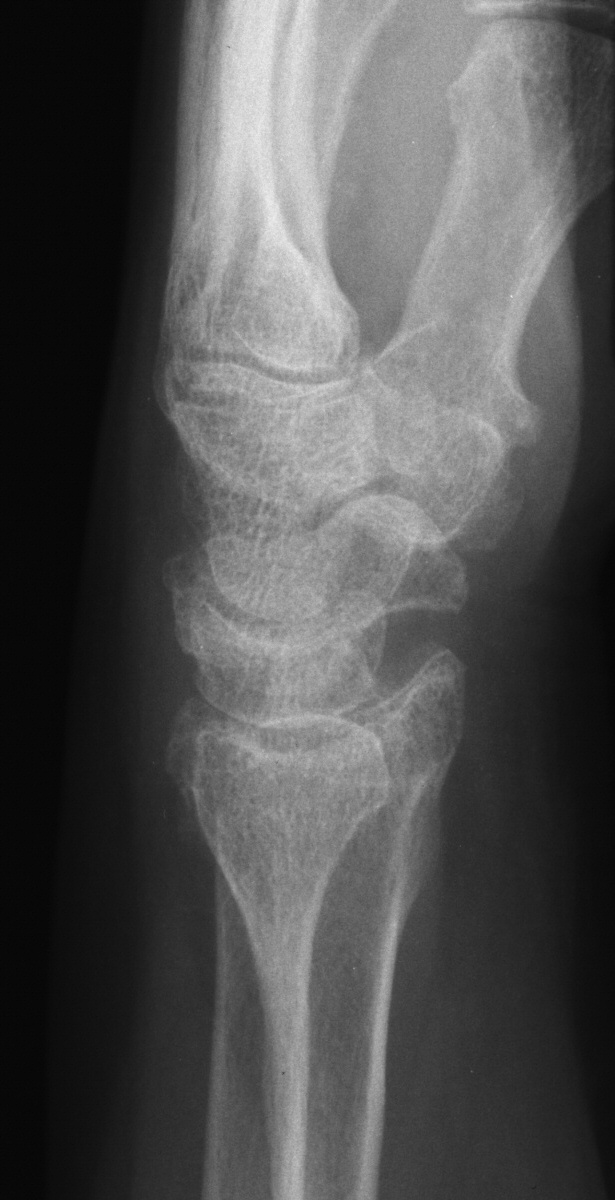

| This patient presented with

persistent wrist pain, swelling and stiffness one year out from closed

reduction and external fixation of a n intraarticular distal radius

fracture. |

| No prior films were

available. Plain films suggested a depressed section of the radial edge

of the lunate fossa and loss of dorsal tilt. |

| On first glance, 3D CT

reconstruction looked favorable for possible simple dorsal opening

wedge corrective osteotomy. |